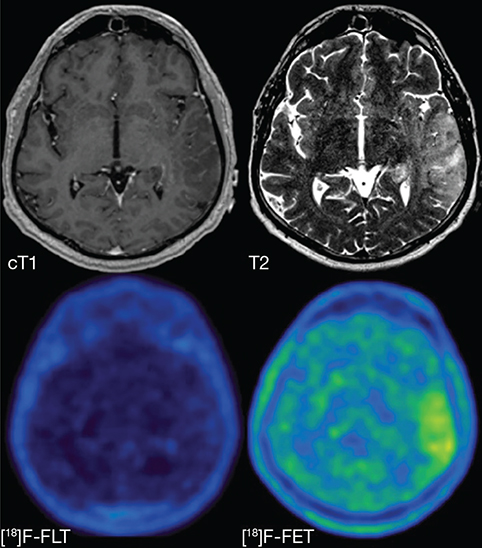

All four nucleoside-based agents – 18F-FLT, 11C-4DST, 18F-FMAU and 11C-TdR – are based on thymidine, which pairs with adenine in the DNA double helix and is therefore directly involved in cellular proliferation. These agents use equilibrative nucleoside transporter 1 (ENT1) to enter cells (Figure 5). Although ENT1 is present throughout the brain including endothelial cells (Table 3), none of these agents can readily cross the BBB leading to a high T/N ratio. In clinical practice, uptake of either agent will therefore reflect at least increased BBB permeability next to ENT1 overexpression (105). After entering the cell, most become phosphorylated by thymidine kinase 1 (TK1), which is cell-cycle dependent and therefore upregulated in tumor cells, or TK2, which is restricted to mitochondria and is cell-cycle independent. Only 18F-FLT and 11C-4DST interact with TK1: 18F-FLT subsequently becomes trapped in the cytoplasm because it lacks an essential hydroxyl group, causing uptake to indirectly reflect increased cellular proliferation, while 11C-4DST becomes incorporated into DNA, thereby directly reflecting increased DNA synthesis and proliferation (Figure 5) (105). Kinetic analyses will be necessary to distinguish uptake due to disrupted BBB from that due to increased cellular proliferation(106), decreasing their sensitivity for brain tumor cells compared to amino acid agents like 11C-MET and 18F-FET (Figure 6), and they should not be used for e.g., recurrent non-enhancing brain tumors (107, 108). However, uptake of 18F-FLT has been shown to differentiate between grade III and IV gliomas, and is sometimes seen in non-enhancing areas on MRI, suggesting not all uptake is BBB-related; it has also been suggested that even a small number of glioma cells can cause BBB disruption without additional contrast agent leakage (108, 109). Tumor uptake of 18F-FLT can also be used to predict tumor progression in meningiomas (110). Background uptake of 11C-4DST is paradoxically high compared with 18F-FLT, and it has not been studied much (111). 18F-FMAU becomes phosphorylated by TK2, raising the question whether uptake really reflects cellular progression, while 11C-TdR is not used anymore because of its high catabolism into 11C-CO2 which causes significant background uptake.

Figure 6. T1-weighted post-contrast (cT1), T2-weighted (T2), 18F-FLT PET ([18]F-FLT) and 18F-FET ([18]F-FET) images of a patient with a non-enhancing glioblastoma, WHO grade IV. The lesion is hyperintense on the T2-weighted image but does not show contrast enhancement. Increased uptake in the T2-hyperintense region can clearly be seen on the 18F-FET PET image, but there is no uptake visible on the 18F-FLT PET image, illustrating the drawback of PET agents that cannot easily cross the BBB. This figure is reproduced – with new figure legend appropriate for current article – from Nowosielski et al. (2014), Figure 1, under the terms of the Creative Commons Attribution 4.0 International (CC BY) License (http://creativecommons.org/licenses/by/4.0) (107).